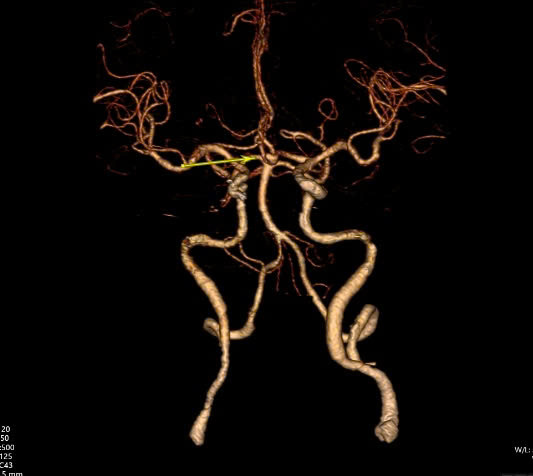

Ngay khi tiếp nhận, các bác sĩ đã chụp CT não có dựng hình mạch máu để kiểm tra thì phát hiện tình trạng xuất huyết khoang dưới nhện do vỡ phình mạch máu ở đoạn động mạch não thông trước, kích thước túi phình lớn nhất là khoảng 7mm và có nhiều múi.

Để xử lý bệnh cảnh này, các bác sĩ khoa Sọ Não Cột Sống 2 đã quyết định phẫu thuật kẹp cổ túi phình nhằm loại trừ túi phình ra khỏi hệ thống mạch máu và ngăn tình trạng xuất huyết não tái phát về sau.

Dưới sự hỗ trợ của kính hiển vi, các bác sĩ tiến hành bộc lộ cổ túi phình để đặt clip ngang cổ phình mạch và loại bỏ túi phình ra khỏi hệ thống mạch máu não mà không ảnh hưởng dòng máu nuôi não. Sự hỗ trợ của kính vi phẫu giúp phẫu thuật viên thao tác nhẹ nhàng, tinh tế, hạn chế tác động mạnh dẫn đến nguy cơ xuất huyết trong lúc mổ."